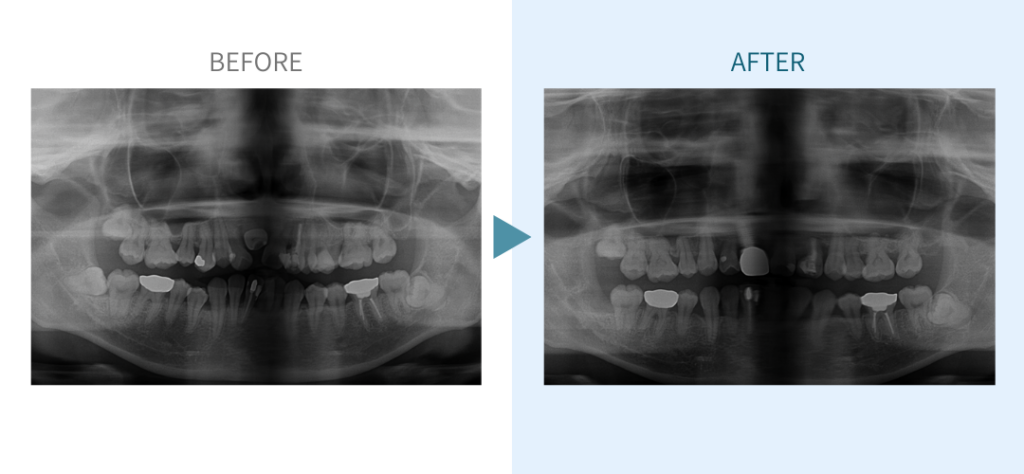

デンタルチームジャパンでは、サイナスリフト(上顎洞底挙上術)や骨造成など、他院で「骨が足りない」と断られた難症例にも対応しています。

私たちは、難症例に関する治療法を学会でも発表しており、その豊富な実績と技術力が評価され、全国から患者様が来院いただいております。

こちらではその一部の症例についてご紹介します。